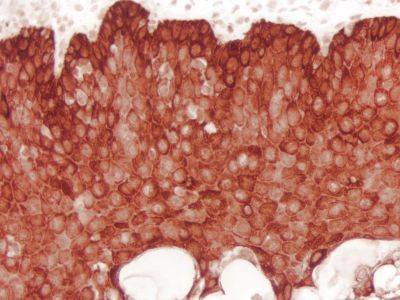

The?M.O.M. ImmPRESS Kit contains our proprietary M.O.M. Mouse Ig Blocking Reagent paired with a specialized, ready-to-use, one-step M.O.M. ImmPRESS Peroxidase Polymer reagent. It provides a significant reduction of endogenous mouse Ig staining when using mouse primary antibodies on mouse tissue.

For years, researchers attempting to localize mouse primary antibodies on mouse tissue have relied on the Vector??M.O.M. Kit to produce crisp, strong, specific staining of antibody targets. ?The?Vector?M.O.M. Kits are specifically designed to significantly reduce endogenous mouse Ig staining when using mouse primary antibodies on mouse tissue. ?The inability of an anti-mouse detection antibody to distinguish between a primary antibody produced in mice and the endogenous mouse immunoglobulins present in mouse tissue results in high background staining which obscures specific staining. ?This problem can be essentially eliminated by using?Vector?M.O.M. Kits. ?The result is clear, crisp staining of the antigens of interest. ?Tedious calculations and primary antibody pre-binding steps are not required.

The M.O.M. ImmPRESS HRP polymer reagent is affinity purified and specifically optimized for use with the?M.O.M. Mouse Ig Blocking Reagent. ?The highly active peroxidase micropolymers of the?ImmPRESS Detection System provide outstanding sensitivity, limit steric interference, and enhance accessibility. ?Excellent staining results for a once difficult application have now become routine with the?Vector?M.O.M. System.